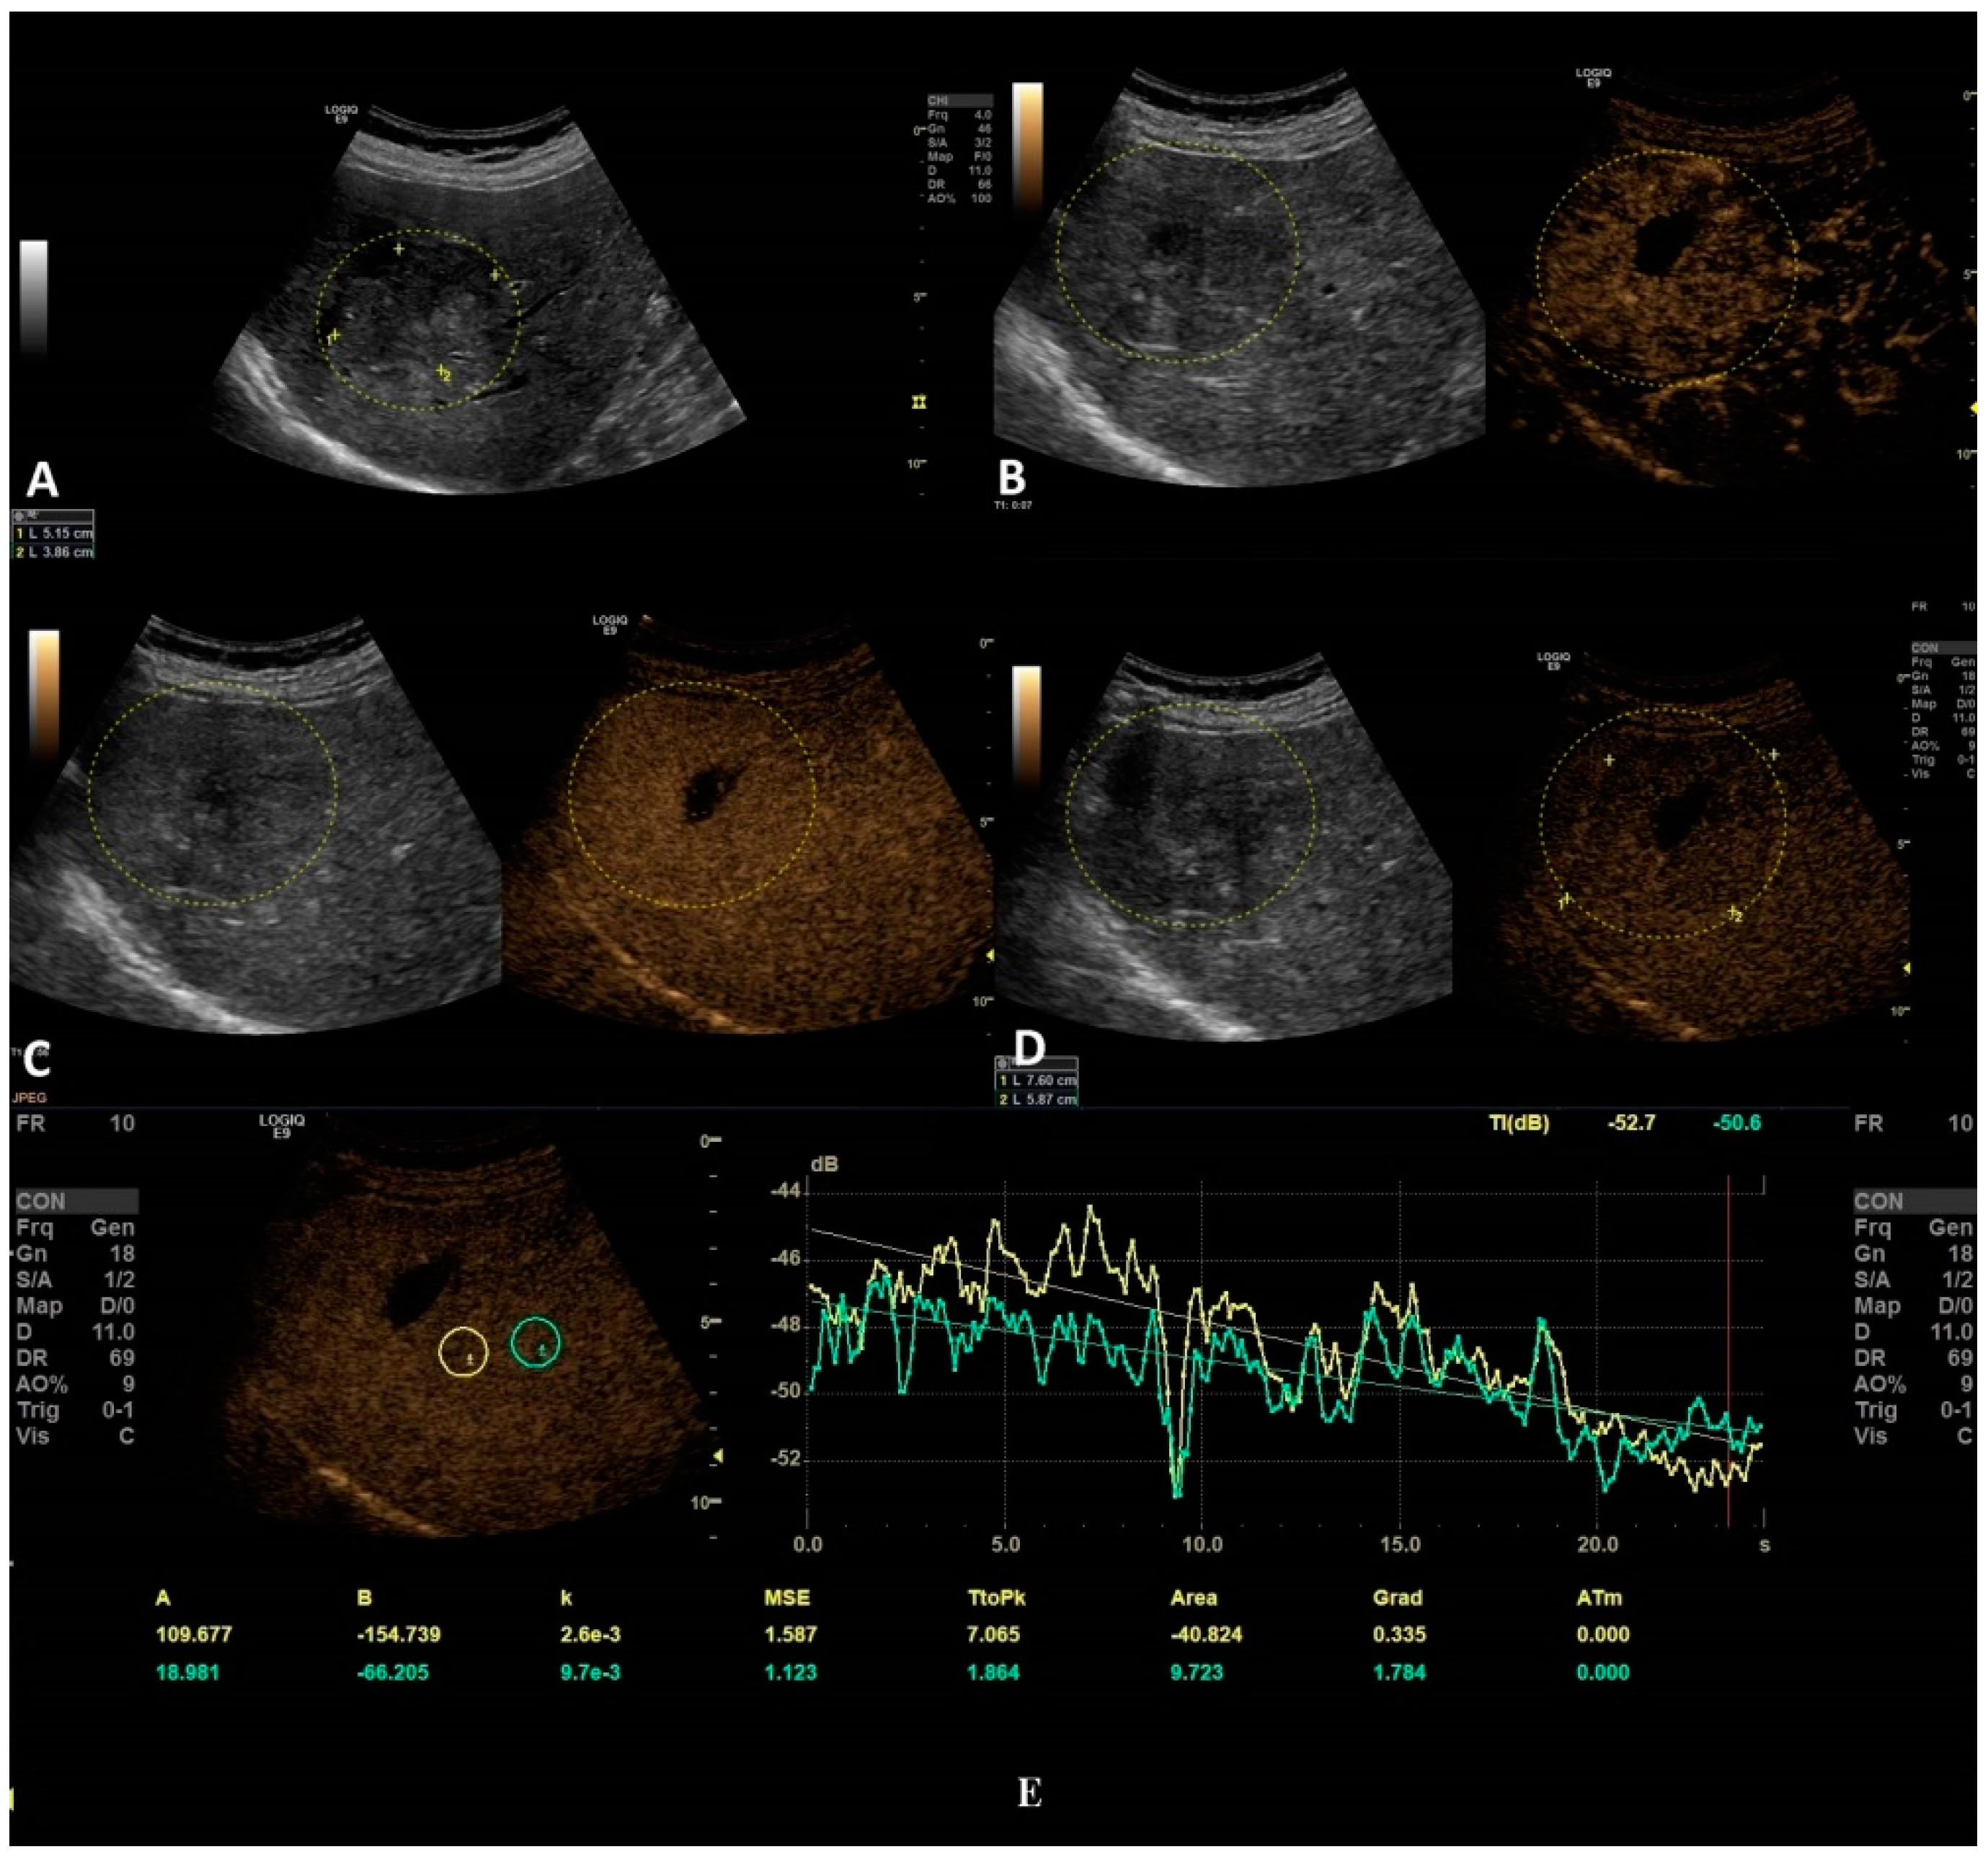

Figure 5.

In this setting, a malignant lesion was assessed, as depicted in B-mode (A). CEUS evaluation is depicted in frames (B–D). In frame (D), the enhancement pattern is not recognizable; thus, TIC analysis (E) was applied. The results revealed objective washout phenomena (the graphs are intersecting one another).